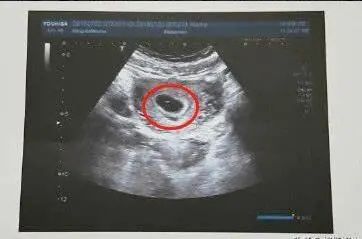

以上项目中,NT、早中期的唐筛、四维B超均为基础的排畸项目,NT异常提示胎儿染色体异常可能,唐氏筛查主要是排除胎儿患21-3体,18-3体及开放性神经管畸形的风险,听说过唐氏儿吗?这个病的另一个名字叫“先天愚型”,它是人类最早发现、最常见的染色体畸形,这个病的特征是:智力落后、特殊面容和生长发育迟缓,常合并多种畸形。